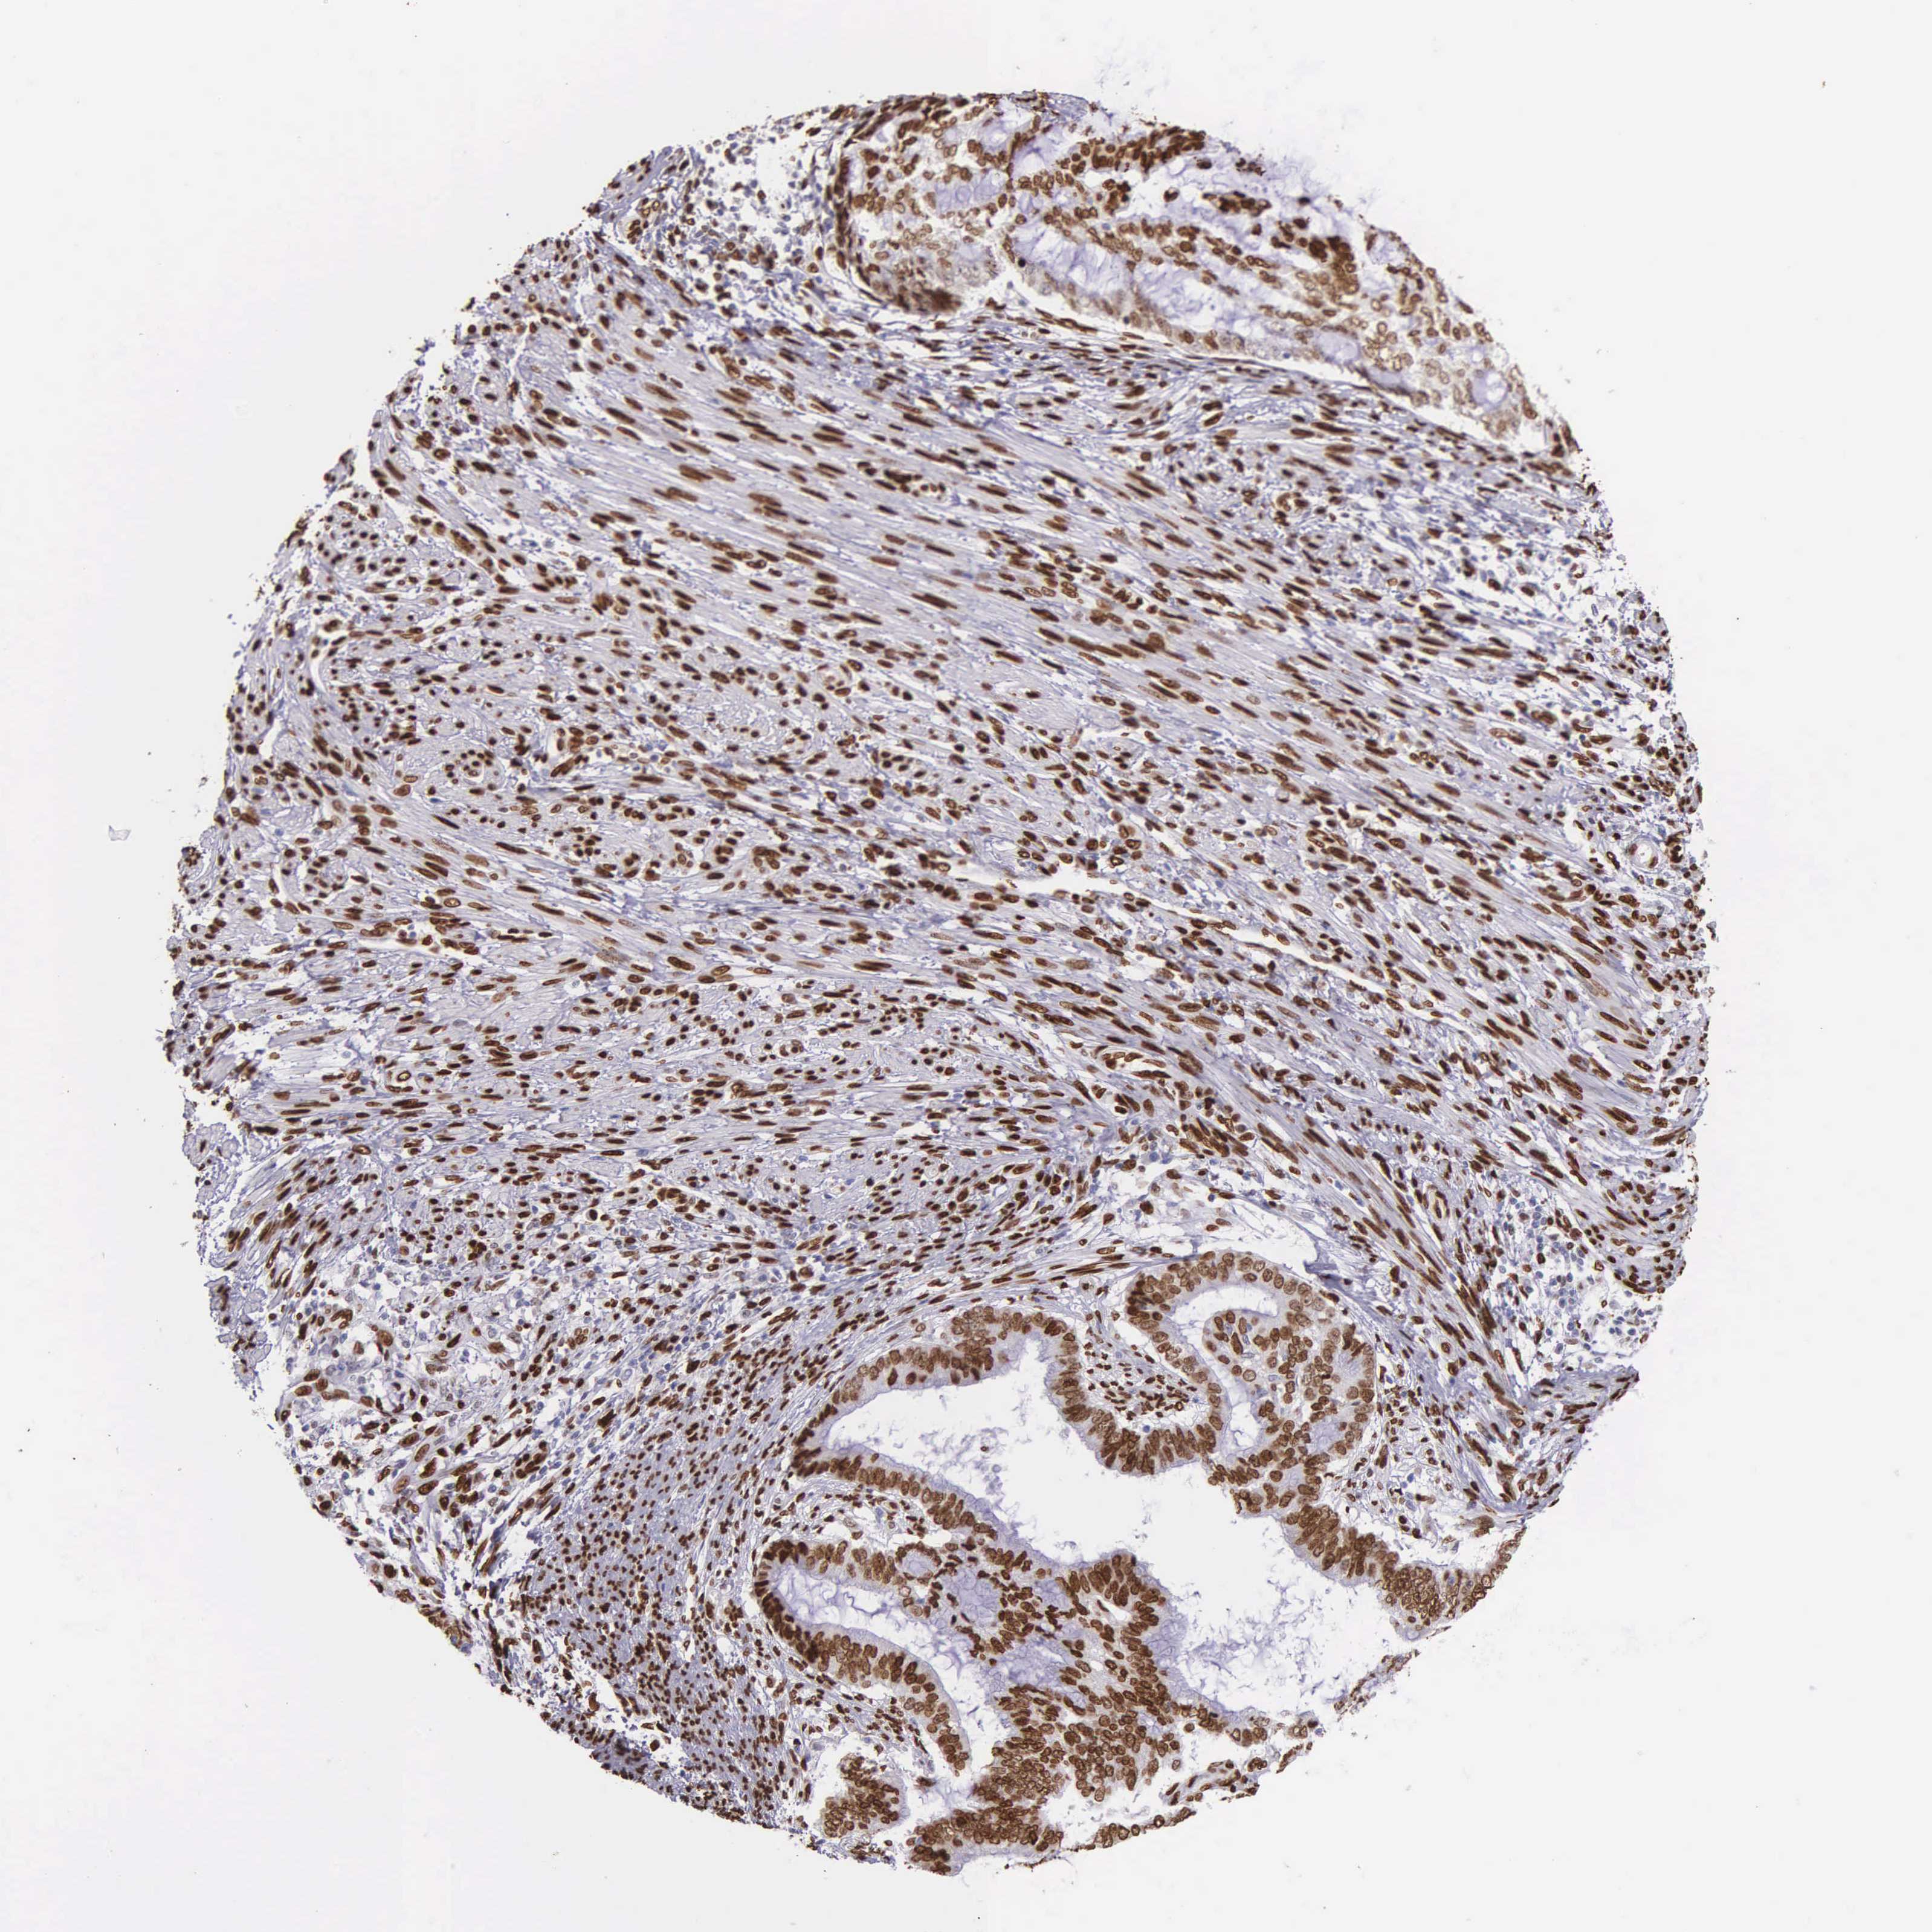

ENDOMETRIAL CANCER - Protein expressioni

A mouse-over function shows sample information and annotation data. Click on an image to view it in a full screen mode. Samples can be filtered based on level of antibody staining by selecting one or several of the following categories: high, medium, low and not detected. The assay and annotation is described here.

Note that samples used for immunohistochemistry by the Human Protein Atlas do not correspond to samples in the TCGA dataset.

Antibody stainingi

Antibody staining in the annotated cell types in the current human tissue is reported as not detected, low, medium, or high, based on conventional immunohistochemistry profiling in selected tissues. This score is based on the combination of the staining intensity and fraction of stained cells.

Each image is clickable and will lead to virtual microscopy that enables deeper exploration of all samples and also displays staining intensity scores, fraction scores and subcellular localization as well as patient and tissue information for each sample.

Antibody HPA000843

Staining

High

Medium

Low

Not detected

Intensity

Strong

Moderate

Weak

Negative

Quantity

>75%

75%-25%

<25%

None

Location

Nuclear

Cytoplasmic/membranous

Cytoplasmic/membranous,nuclear

Adenocarcinoma, NOS